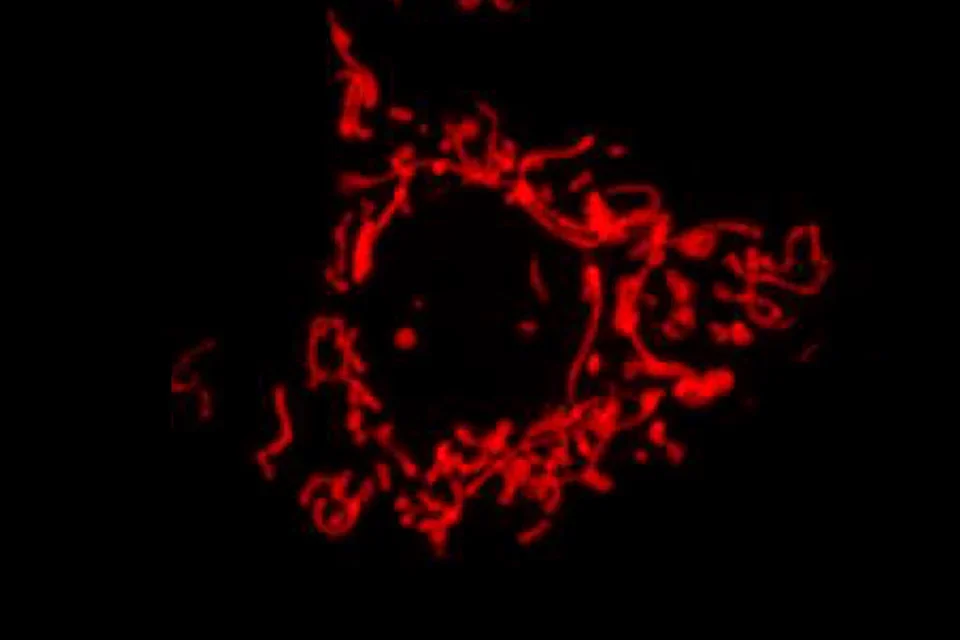

ATP is the universal currency of energy. Double-membraned organelles called mitochondria create ATP by processing nutrients in two units:

- A combustion unit that burns nutrients and uses the resulting energy to charge a battery.

- An electrical engine unit that, under the direction of a protein called ATP synthase, uses the battery’s charge to make ATP.

“The mitochondria combust nutrients and use the energy of combustion to electrically charge its membrane,” Shirihai explains. “It then uses the electrical charge to spin the turbine and produce ATP. In a way, mitochondria are like a hybrid car, combining an engine with a battery. The engine burns the fuel to spin a turbine to charge a battery.”